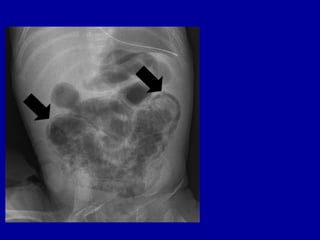

Portal Air

Dilated stomach &

RADIOLOGICAL FINDINGS

• Portal Venous Gas

– extension of pneumatosis intestinalis into the

portal venous circulation

• linear branching lucencies overlying the liver and

extending to the periphery

• associated with severe disease and high mortality